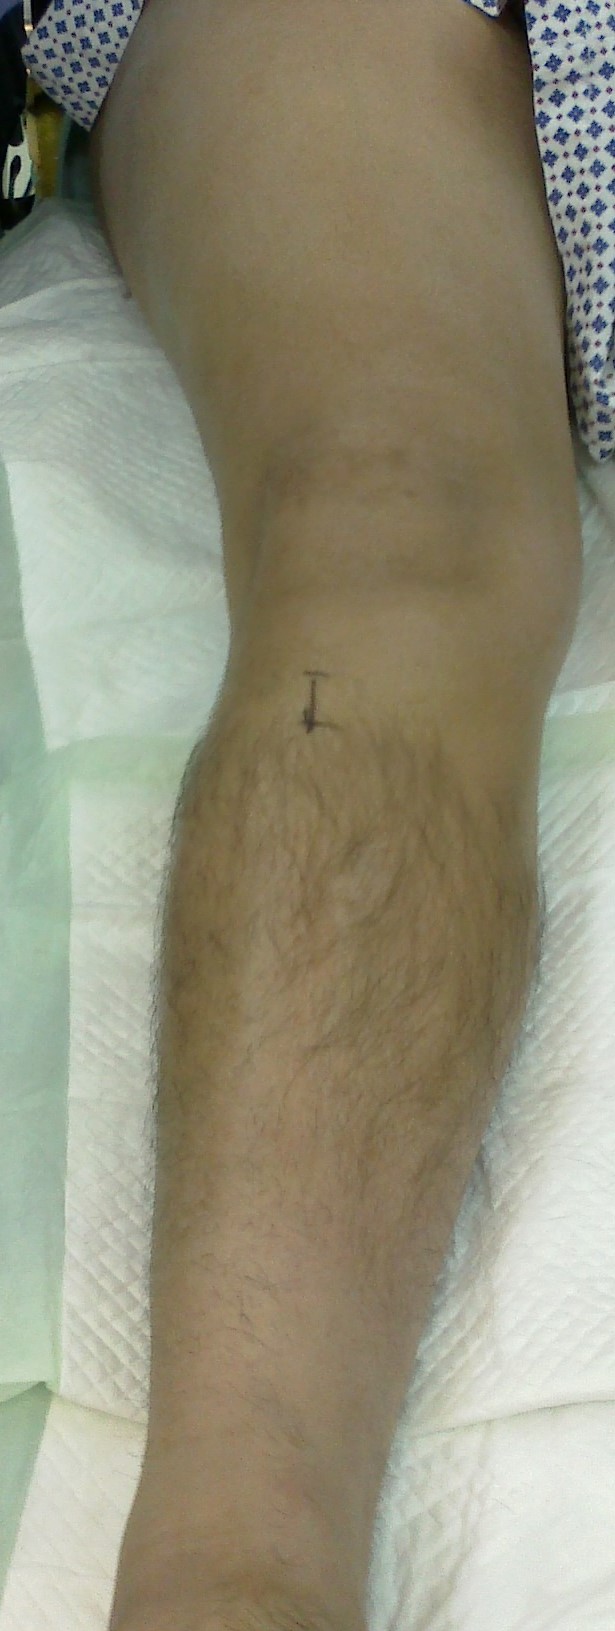

The surgeon in preparation for each surgery preconstructs a customized apparatus. Using wires or pins, the apparatus is surgically attached to the affected limb. Surgery is usually performed percutaneously through small incisions. Special care is taken to minimize injury to the bone and surrounding soft tissue, nerves and blood vessels when making specialized bone cuts.